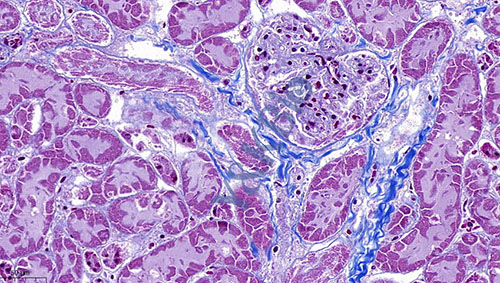

吉林Masson染色是病理染色服务中比较常见的一种,Masson染色用于胶原纤维和肌纤维的染色及鉴定;染色结果:胶原纤维呈蓝色、肌纤维呈红色、细胞核呈蓝黑色。